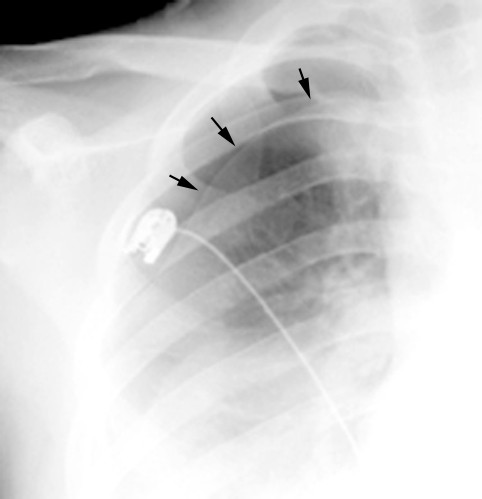

CASE PRESENTATION 39 Years old male – Motorcycle VS Car Accident 92/10/10 visited ER Chest pain Dyspnoea Physical Examination Concious – Clear ... Access Document

Car accident on 1 February 1971. On admission he was found to have fractured second and third right ribs and a right-sided tension pneumothorax. An intercostal catheter connected to underwater drain-age was inserted. Initially there was a large air leak but this ceased. ... Read Document

Posttraumatic pneumothorax: a case report and review of the literature Mark Malota1*, Markus C Kowarik2, Barbara Bechtold3 and Reinhard Kopp1 involved in a traffic accident. As the unbelted driver of a car, he crashed frontally against another car with approximately 50 km/h. ... Read More

A patient arrives at an emergency room with a traumatic pneumothorax after a car accident. In the course of the accident, the patient suffered a penetration wound which allowed air to fill the space around one of her lungs causing it to collapse. ... Get Document